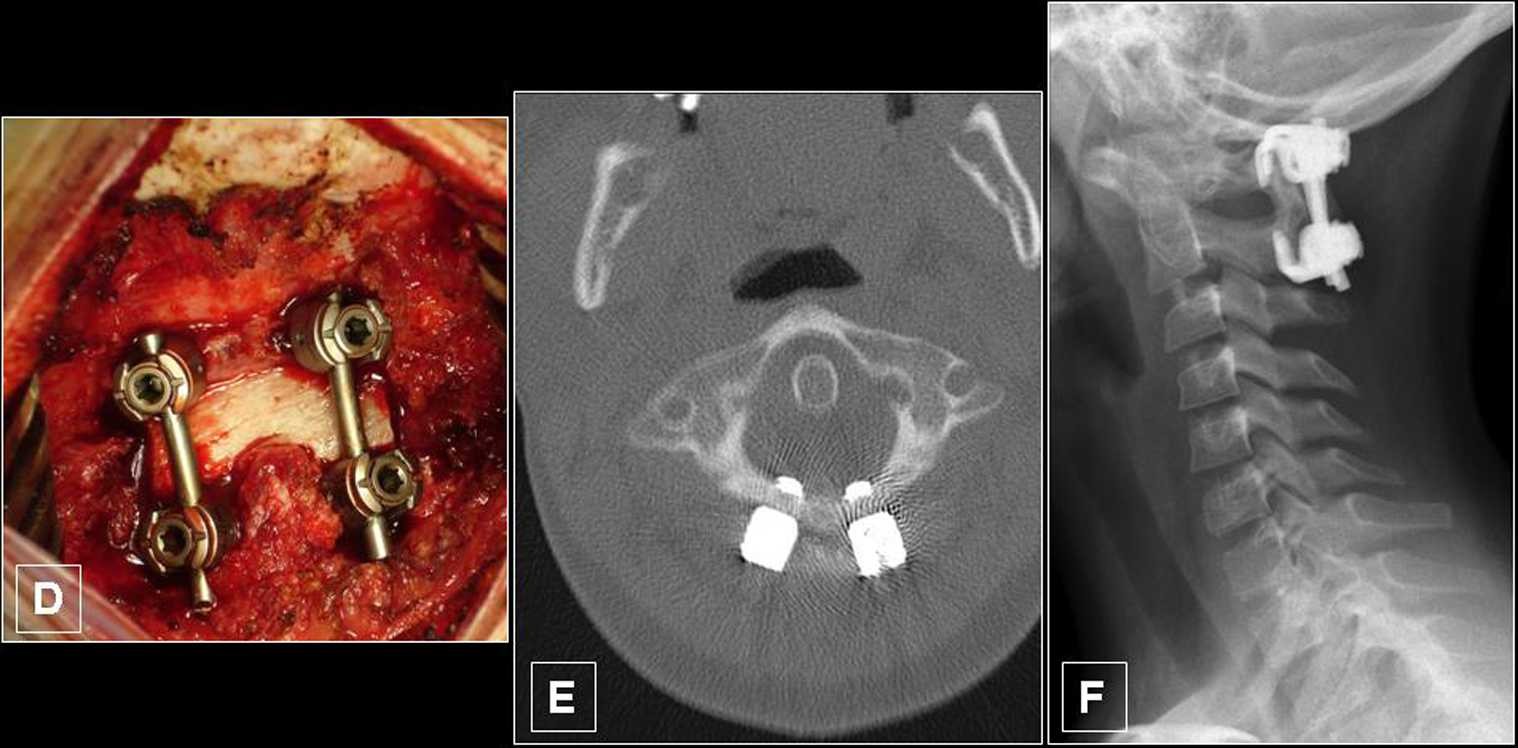

Figure 3 I Traumi Cervicali Del Bambino Springerlink